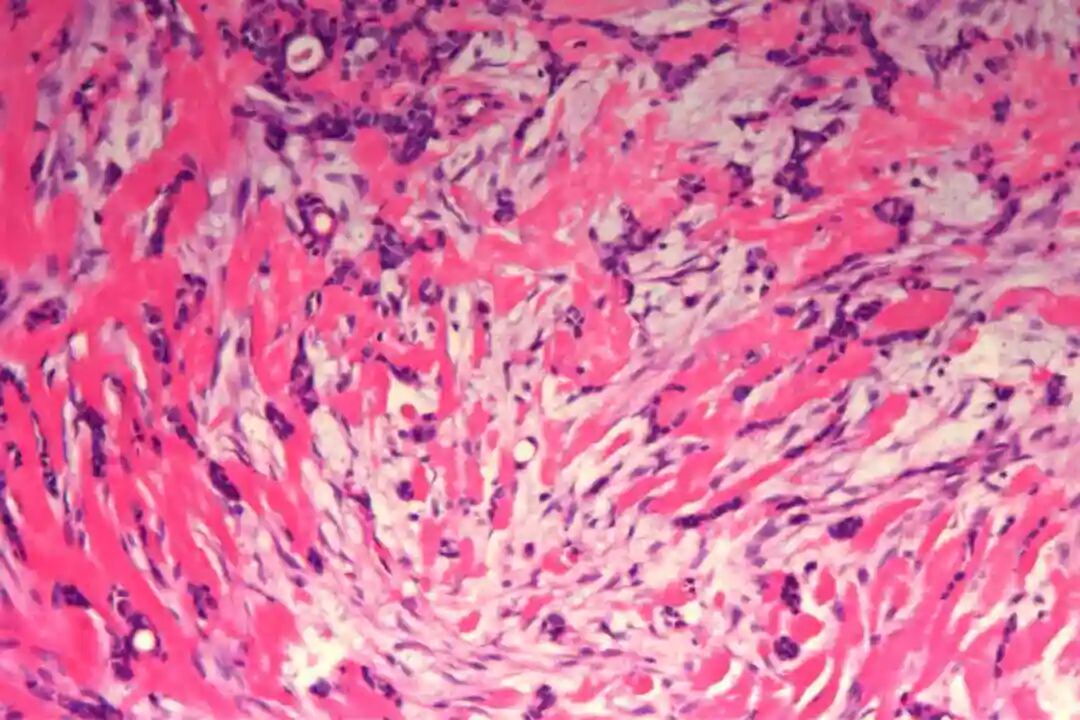

细胞形态:基底样肌上皮细胞体积较小,呈圆形或卵圆形,细胞核深染、染色质均匀,核仁不明显,胞质稀少、淡嗜酸性;腺上皮细胞体积略大,呈柱状或立方状,细胞核淡染、染色质疏松,核仁清晰,胞质丰富、嗜酸性。实性巢团内可见少量微小腔隙,腔隙内可含有少量嗜酸性或嗜碱性黏液样物质(PAS染色阳性),这是实体型与其他实性肿瘤的重要鉴别点;核分裂象少见,一般≤5个/10HPF,部分实体型区域可出现轻度至中度细胞异型性,但无明显恶性增殖活性表现,与高级别乳腺癌的细胞异型性有明显区别。

实体型区域与经典型区域无明显明确界限,相互穿插分布,实体型巢团可逐渐过渡为经典型的筛状或管状结构,两种区域的细胞成分相互延续,均可见腺上皮细胞与肌上皮细胞的混合存在,无明显细胞异型性差异(实体型区域异型性略高于经典型,但整体温和)。这种混合性形态是本病的重要镜下特点,也是与单纯实体型PACC、单纯经典型PACC的主要区别。

病理诊断:(左)乳腺:符合腺样囊性癌,实体型为主,部分经典型;肿块大小约5.5x4.5x3.2cm,神经见癌侵犯,脉管内未见癌栓;标本上、下、内、外、表面及基底切缘均未见癌;乳头见癌累及。